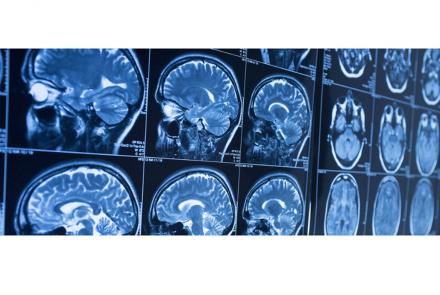

A new $10-million investment from the Ludmer Family Foundation will establish the Ludmer Centre Heritage Fund and help launch and support a Global Brain Consortium of leading brain research institutions focused on sharing infrastructure, methodologies and results, ultimately accelerating treatment for patients.